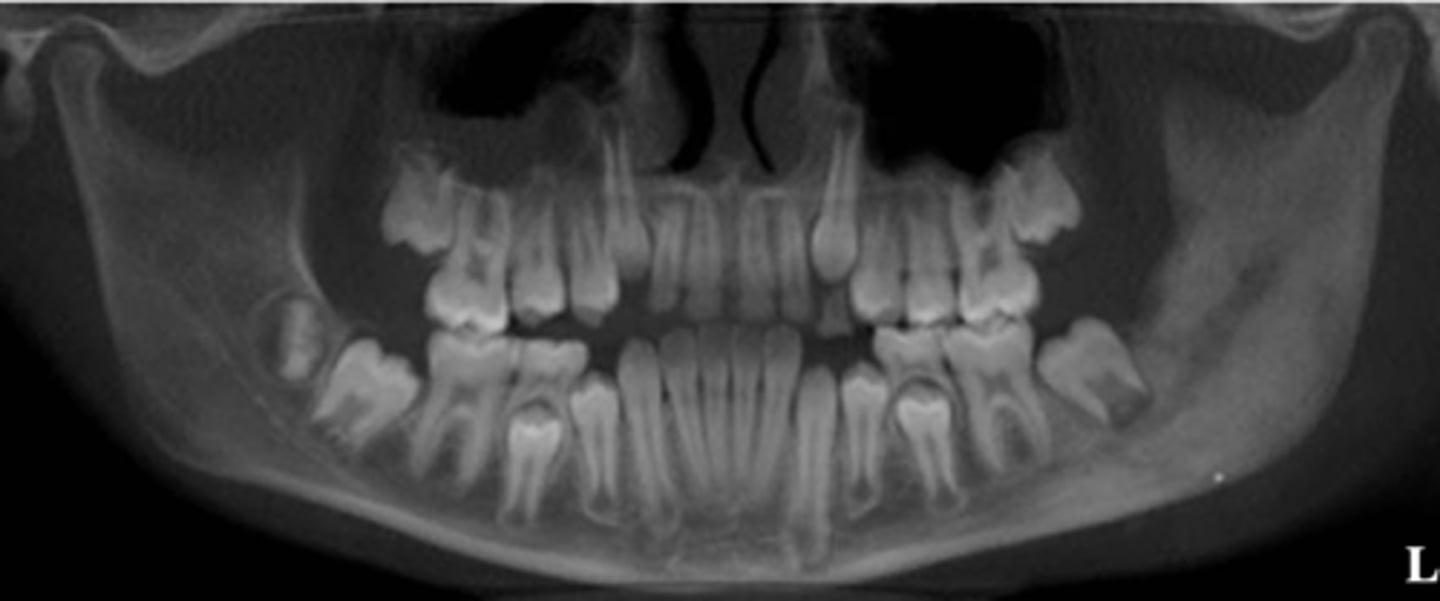

What is the differential diagnosis of the left angle-ramus of mandible?

diffuse sclerosing osteomyelitis (chronic osteomyelitis)

A patient's pano is shown and presents with wrist symptoms. What is the differential diagnosis?

SAPHO Syndrome